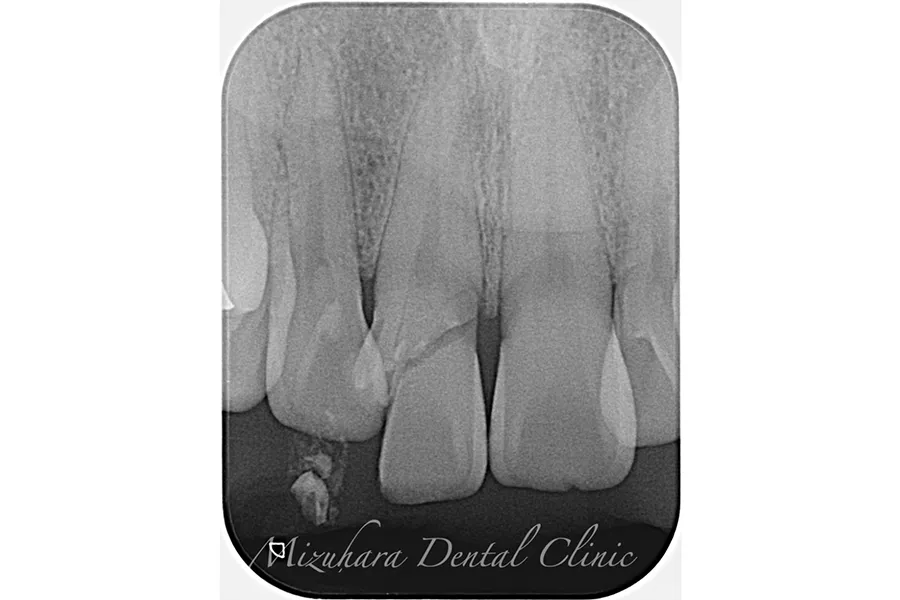

CASE.1

治療前

治療中

治療後

| 担当医 | 水原 翔 |

| 主訴 | 左下の奥歯が腫れて、揺れてる。 抜歯するしかないと言われたが、他に方法がないか相談したい。 |

| 期間 | 精密根管治療:2回 再生療法:1回 被せ物:2回 |

| 費用 | 379,500円 (精密根管治療:132,000円+支台築造:22,000円 +再生療法:110,000円+レーザー:5,500円+被せ物:110,000円) |

| 治療内容 | 精密根管治療 再生療法(歯周病によって骨が無くなった部分に骨を足す治療) 被せ物:オールセラミッククラウン |

| 治療に伴うリスク | 術後は痛み、腫れ、などの副作用が生じる場合があります。 症状が再発する可能性があります。 |